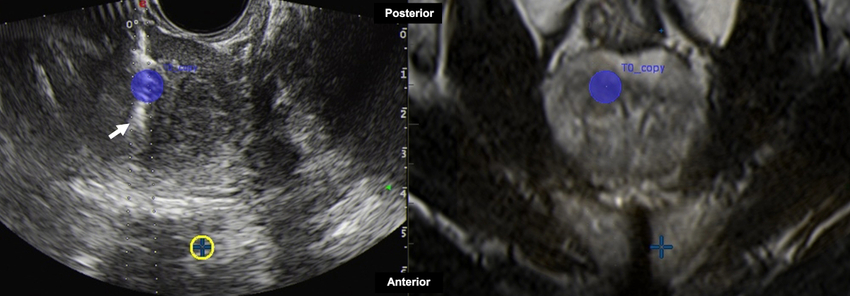

Figura 23

Varón de 56 años con diagnóstico de prostatitis crónica y antígeno específico de próstata en aumento. Biopsia transrectal (flecha) con ecografía por fusión de imágenes (con resonancia magnética). Área objetivo (círculo azul), PIRADS 3, en ecografía (izquierda) y resonancia magnética (derecha). Aguja utilizada: Pro-Mag 18 G (sistema automático). Diagnóstico definitivo: adenocarcinoma, Gleason 7 (3 + 4).